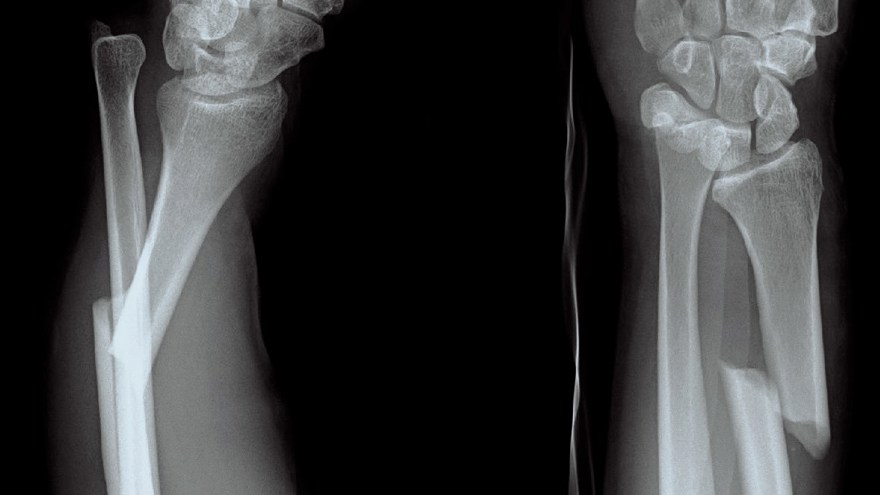

Distal radiusfraktur (handled)

Distal radiusfraktur är den vanligaste frakturen överhuvudtaget. Drabbar oftast kvinnor med osteoporotiskt skelett (fallskada inomhus eller utomhus vid halka). Högenergiskador i samband med trafikolyckor och sport drabbar vanligen yngre individer.

Olika distala radiusfrakturer

- Dorsal felställning: Colles fraktur

- Volar felställning: Smiths fraktur

- Volar felställning med intraartikulärt engagemang: Smith-Barton fraktur

Smith fraktur och Smith-Barton fraktur är ofta instabila och kräver rigid fixation, Smith-Barton oftast med volart anbringad frakturplatta. Colles fraktur kan ibland behandlas enklare, exempelvis med dorsal gipsskena. Denna fraktur dislocerar dorsalt, men även med axial kompression av radius. Graden av radiusförkortning anses påverka slutresultatet och kraftig förkortning bör därför reponeras.